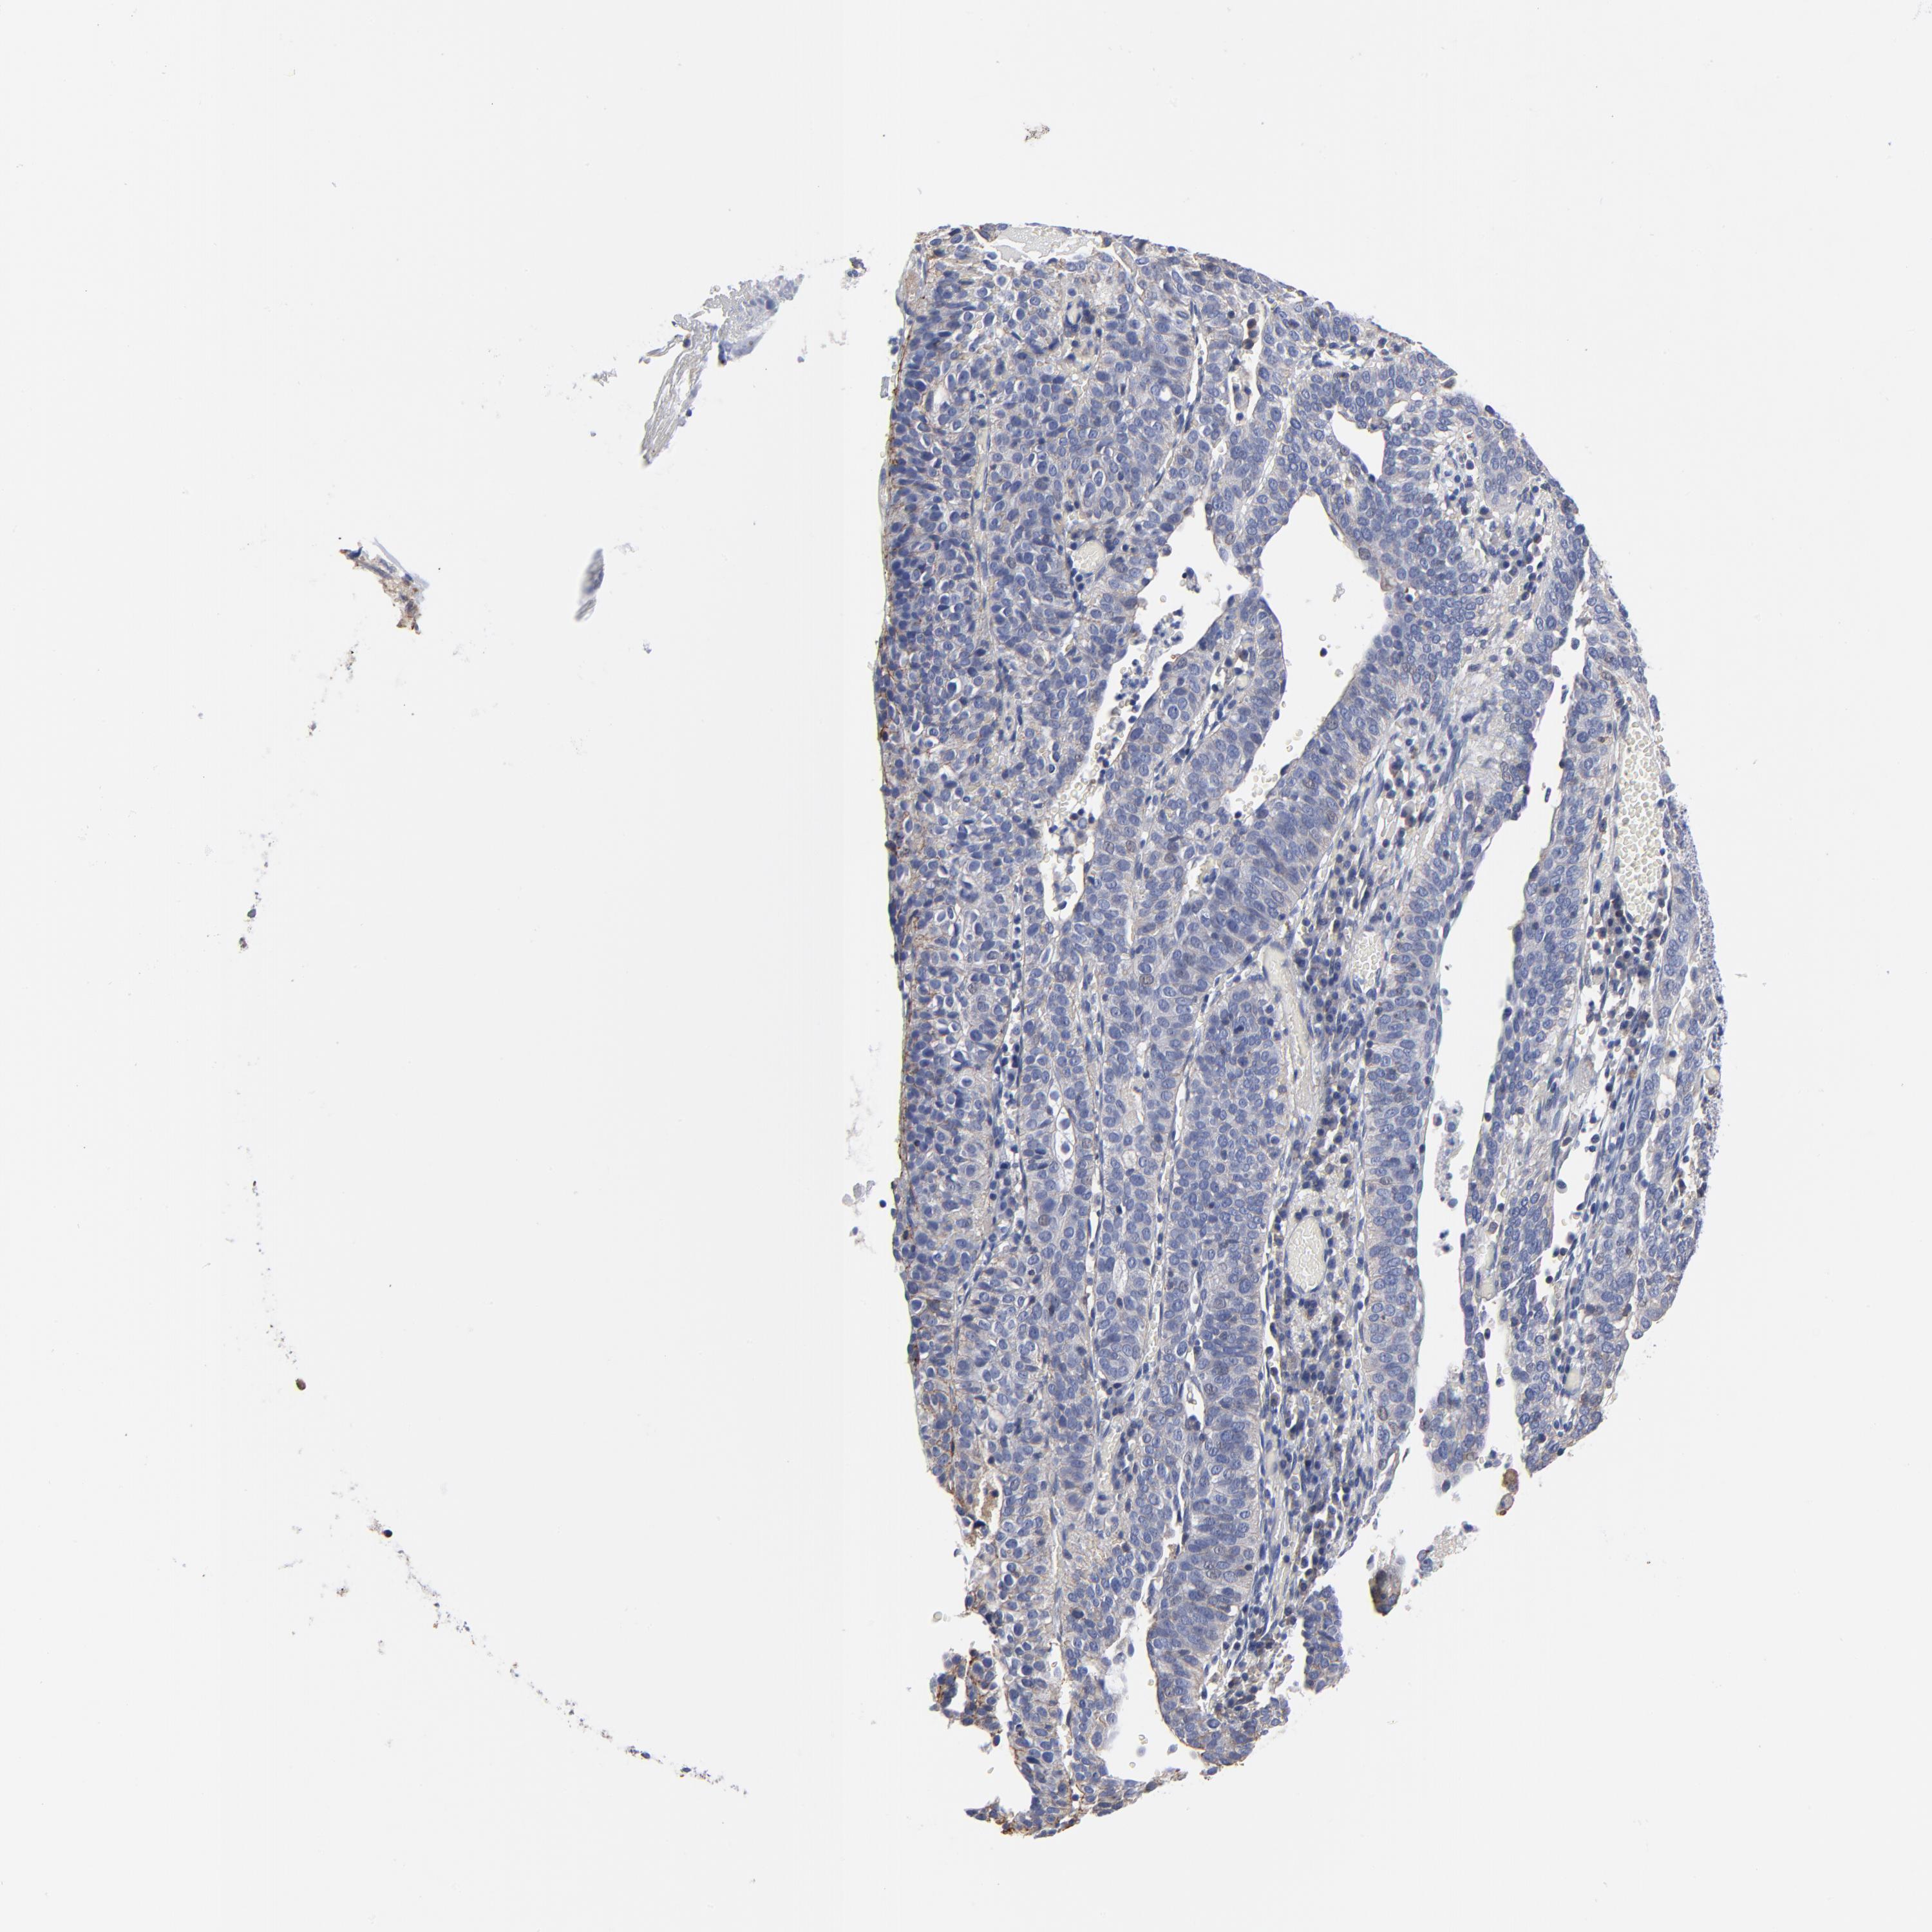

CERVICAL CANCER - Protein expressioni

A mouse-over function shows sample information and annotation data. Click on an image to view it in a full screen mode. Samples can be filtered based on level of antibody staining by selecting one or several of the following categories: high, medium, low and not detected. The assay and annotation is described here.

Note that samples used for immunohistochemistry by the Human Protein Atlas do not correspond to samples in the TCGA dataset.

Antibody stainingi

Antibody staining in the annotated cell types in the current human tissue is reported as not detected, low, medium, or high, based on conventional immunohistochemistry profiling in selected tissues. This score is based on the combination of the staining intensity and fraction of stained cells.

Each image is clickable and will lead to virtual microscopy that enables deeper exploration of all samples and also displays staining intensity scores, fraction scores and subcellular localization as well as patient and tissue information for each sample.

Squamous cell carcinoma, NOS

Adenocarcinoma, NOS